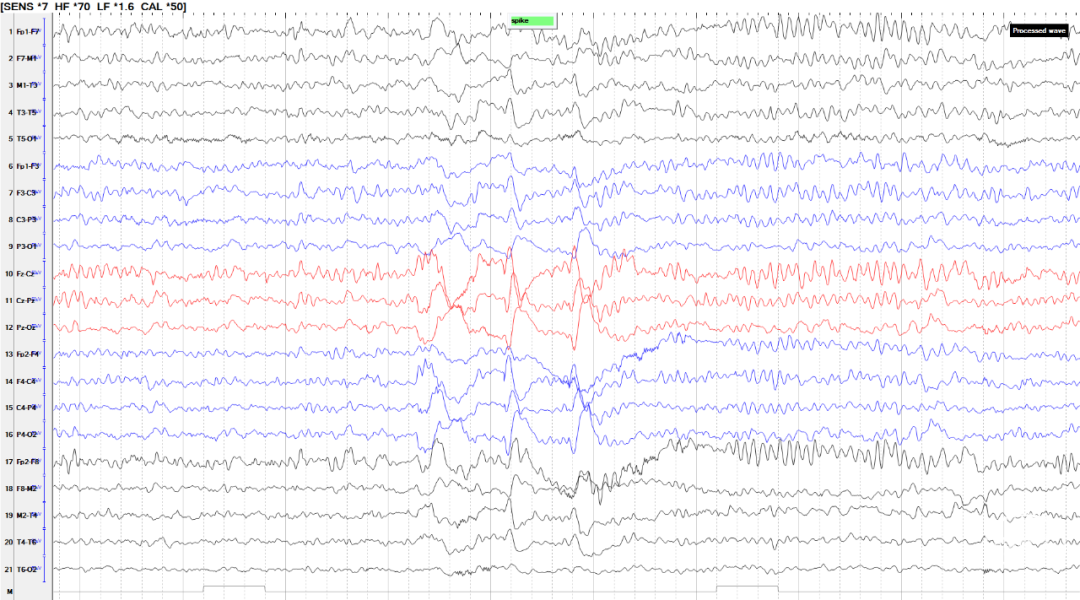

患者于5月龄首发,诱因:发热1周,热峰40℃,表现为发热第1天出现双眼上翻,无肢体抽搐,持续数分钟;15月龄学步后发现行走易跌倒,坐位时出现头颈及躯干向一侧倾斜,每次持续2-3秒,每天发作数次,声音刺激可诱发;病程中仅17岁出现1次全身僵直抖动;23岁后发作较前稍有缓解,声音刺激无发作,平均1-3次/天,表现为:发作性肢体僵直,每次持续2-3秒;患者幼年起病,辗转多家医院仍发作频繁,反复跌倒至头面部频繁外伤。后转求我院,完善脑电图检查提示清醒期背景活动正常(图1),间歇期放电,弥漫性,中线-右旁中线著(图2-3),2天共监测到30次临床发作,表现为强直发作,累及颈肌、躯干、四肢,以左侧肢体为著;同步脑电图示弥漫性低波幅快节律,以中线-右侧旁中线为著(图4-5)。头颅MRI可见双侧岛叶、基底节、枕叶异常信号(图6)。头颅PET见提示多发低代谢区(图7)。

图4-5.发作期脑电图示弥漫性低波幅快节律,以中线-右侧旁中线为著